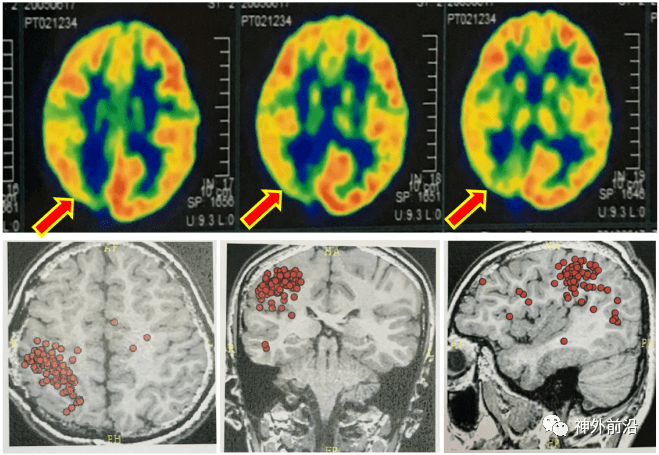

图片来源于网络,如有侵权,请联系删除